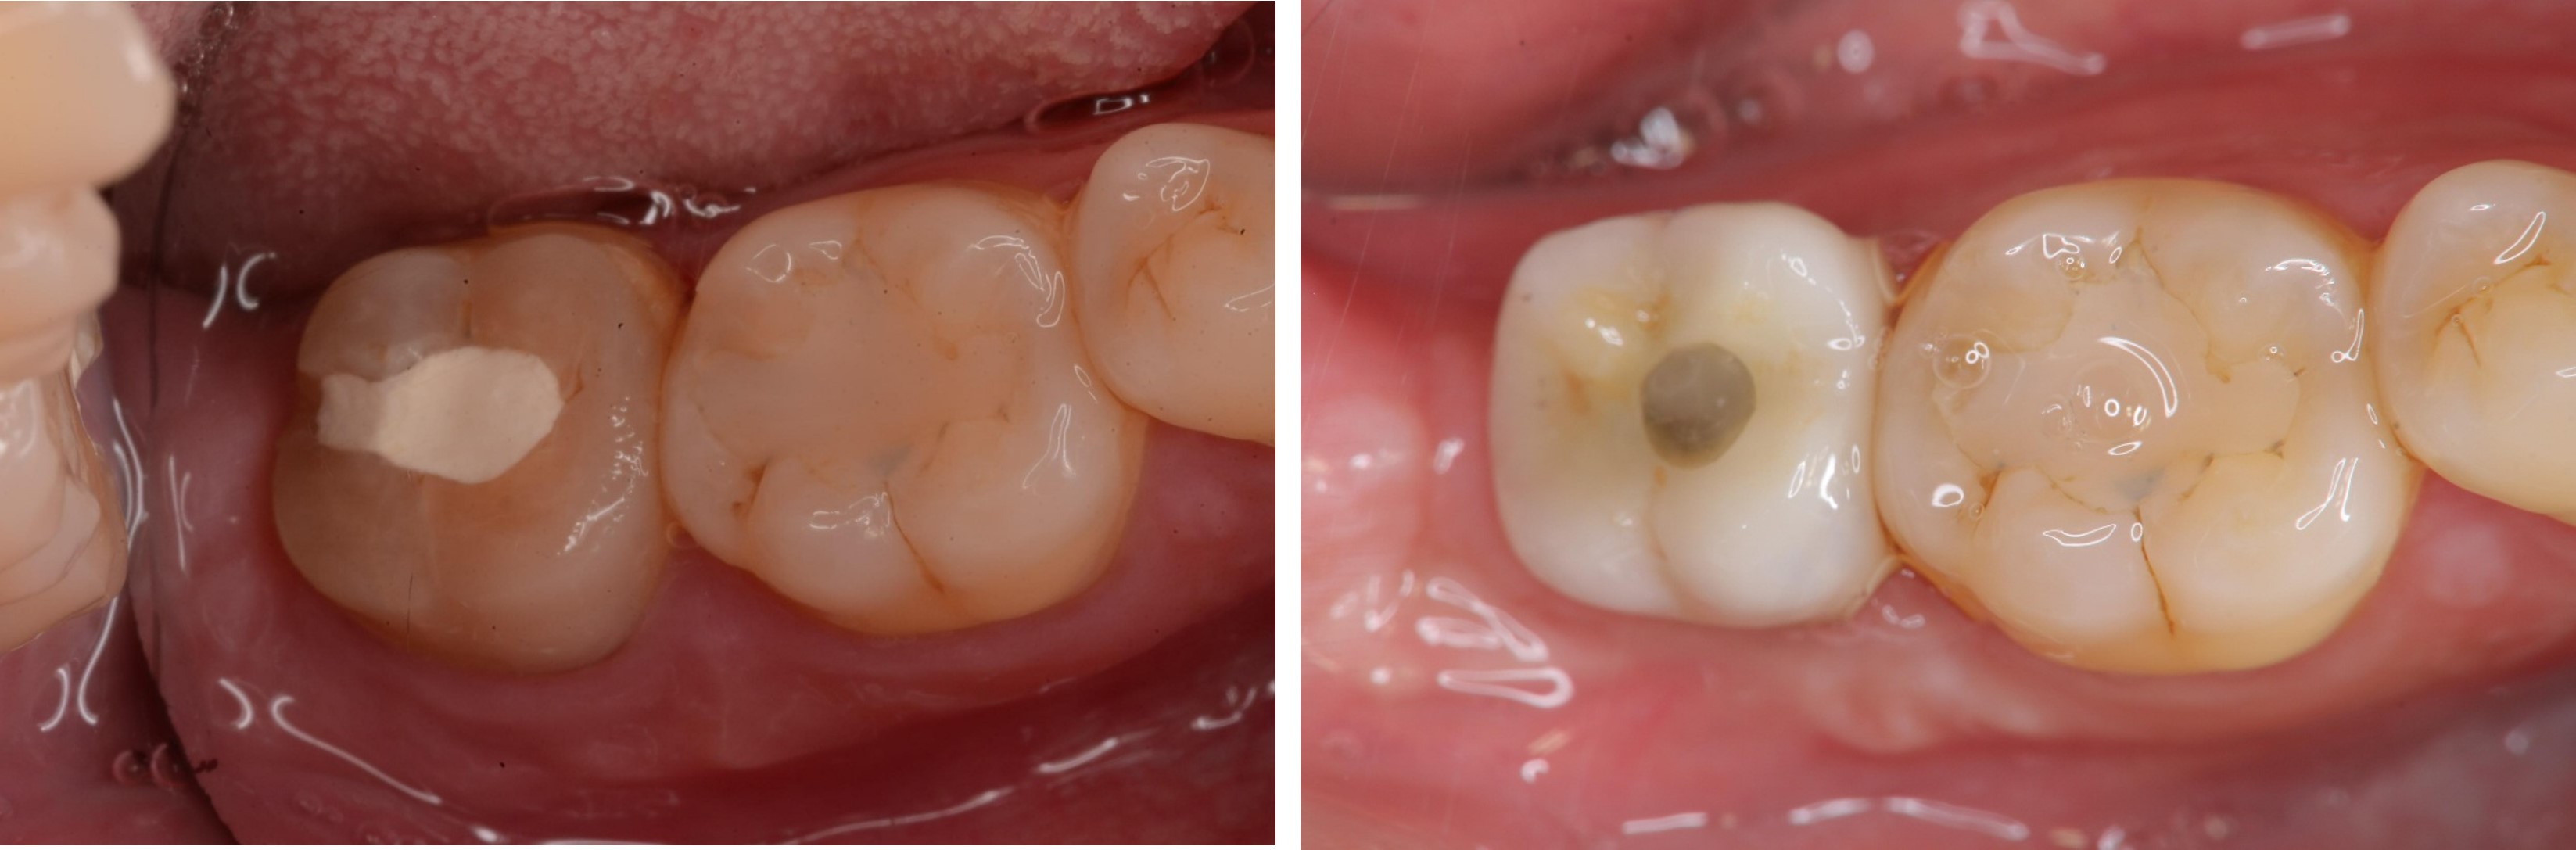

治療後,咬合牙周適應良好

治療後,密合度良好

術前、術後比較